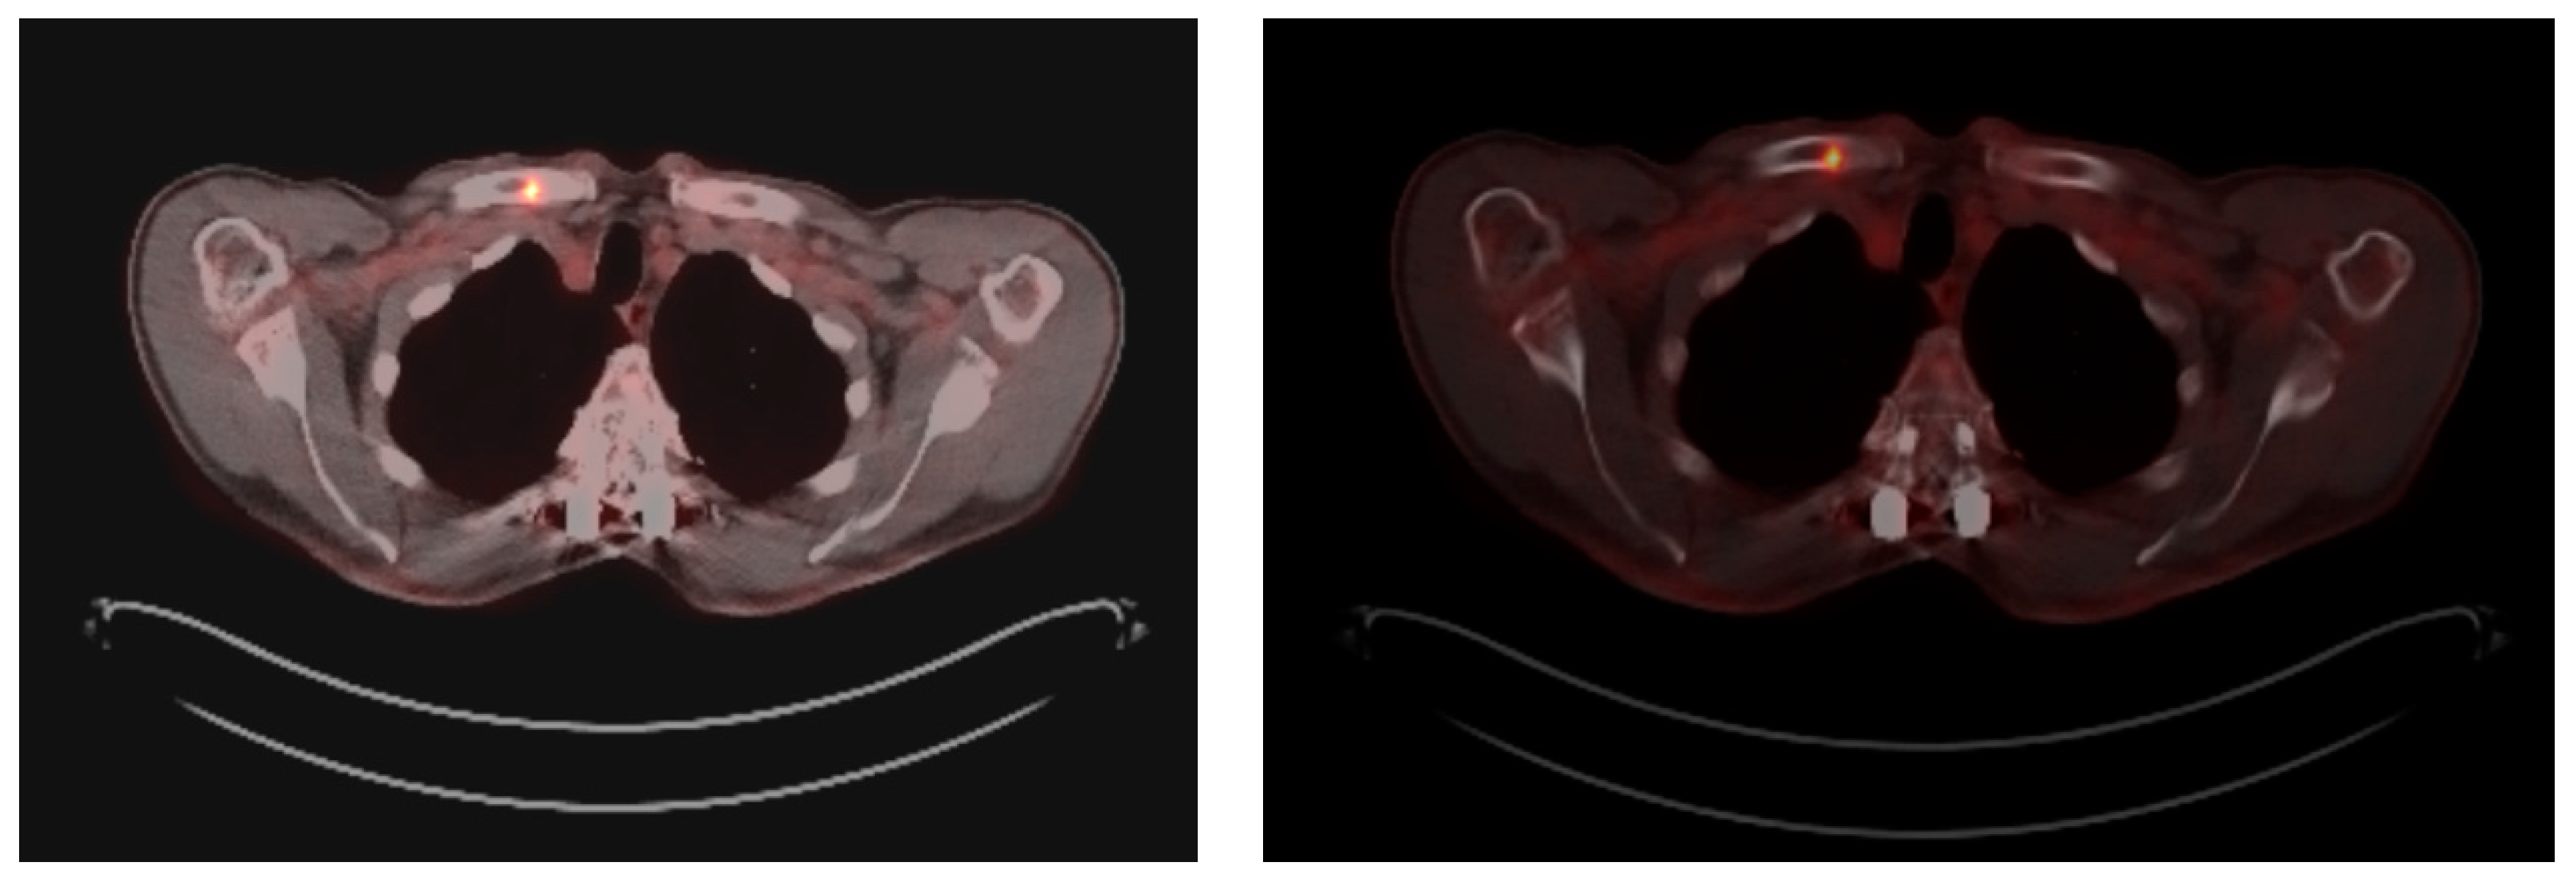

At this moment, the patient was offered (and accepted) to be enrolled in a clinical trial involving the use of single-agent Talquetamab, a bispecific antibody against CD3 and GPRC5D that redirects T cells to mediate the killing of GPRC5D-expressing myeloma cells. By the end of January 2023, after receiving eight cycles of Talquetamab, he achieved CR with no detectable residual disease in the bone marrow by Next-Generation Flow, and the examination by PET/TC showed a complete metabolic response in all the hypermetabolic lesions previously identified. Unfortunately, at the beginning of July 2023, before starting the 15th cycle of treatment, the patient complained again of bone pain in the right shoulder area. A follow-up PET/CT was requested, which showed a hypermetabolic lytic lesion (SUVmax = 7.7) located in the medial third of the right clavicle that was not presented previously and thus suggestive of progressive disease (Figure 2). At this point, no measurable disease was detectable in the serum or urine by SPEP/IFE or mass spectrometry.

Figure 2. Hypermetabolic lytic lesion (SUVmax = 7.7) in the medial third of the right clavicle, not present in the previous study and highly suggestive of progressive disease.